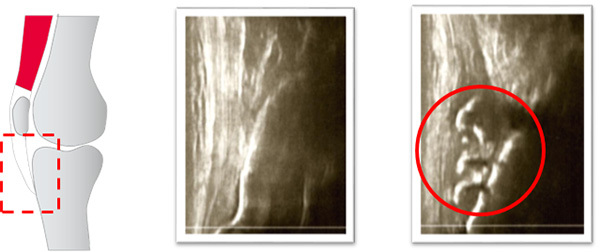

レントゲンでは骨折がはっきりしないことが多い肋骨骨折。

エコー検査を用いて肋骨骨折を観察すると、骨皮質の段差を確認することができる。